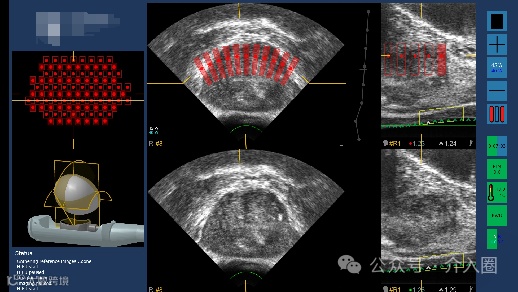

患者情况:69岁,女性,出现胸闷偶伴咳嗽,持续至今仍未好转,影像检查结果提示,患者双肺多处有磨玻璃样结节,直径近1厘米。

治疗结果:在机器人可视影像系统和机械臂穿刺系统的引导下,短短30分钟的手术完成病灶消融。术后患者稍作休息便自行返回病房。